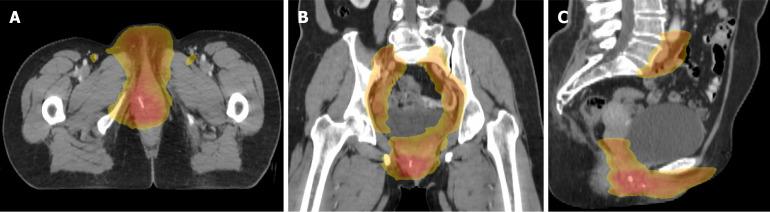

Adenoid cystic carcinoma (ACC) of the Bartholin's gland represents an exceptionally rare malignancy with limited documented cases in the medical literature. It typically manifests as a solid mass that clinically warrants suspicion for neoplastic processes.

This case series details two cases of primary ACC cases involving the Bartholin's gland treated with radical surgical resection of the vaginal lesions. Notably, divergent therapeutic approaches resulted in contrasting prognoses: The patient receiving adjuvant radiotherapy following surgery maintained disease-free status with no locoregional recurrence or metastatic progression through 58 months of surveillance. Conversely, the non-radiated patient experienced disease recurrence within 18 months postoperatively.